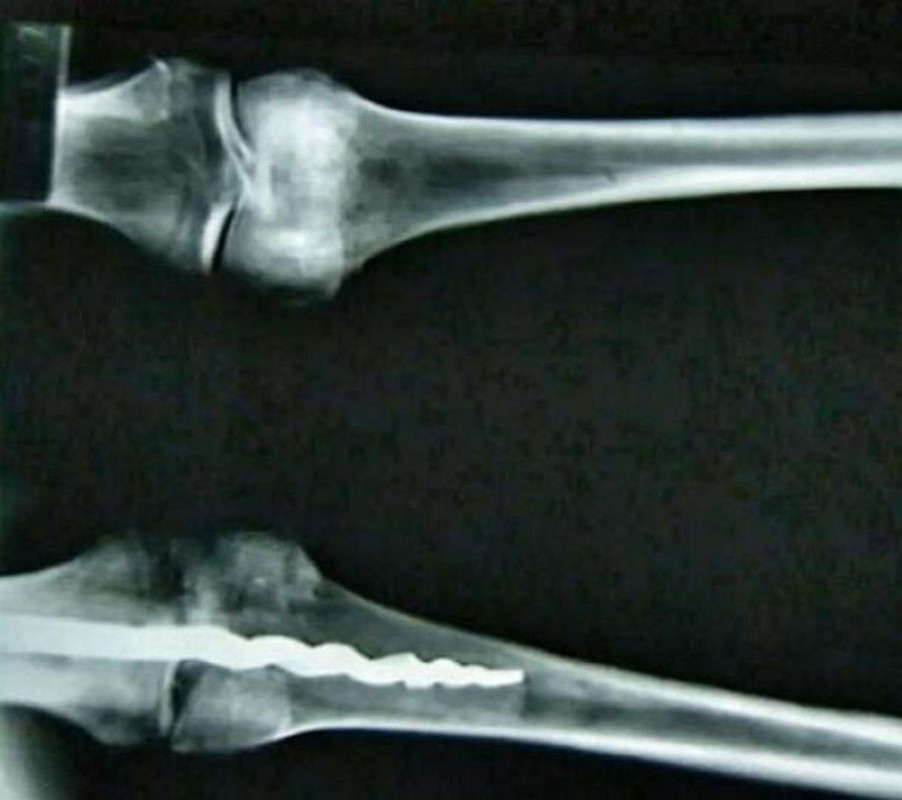

Исследование показало, что 2.600 лет назад египтяне провели сложную хирургическую операцию, запредельного уровня сложности для той эпохи. В колене мумии стоял металлический ортопедический штифт в 23см.

Вполне современная технология, которая была известна древним египтянам, но неизвестна их потомкам. Слишком много накапливается технологий, которые показывают высокий уровень развития древних народов и последующее забвение. Фактически, человечество вынуждено переоткрывать давно известные, но утраченные знания тысячелетней давности.